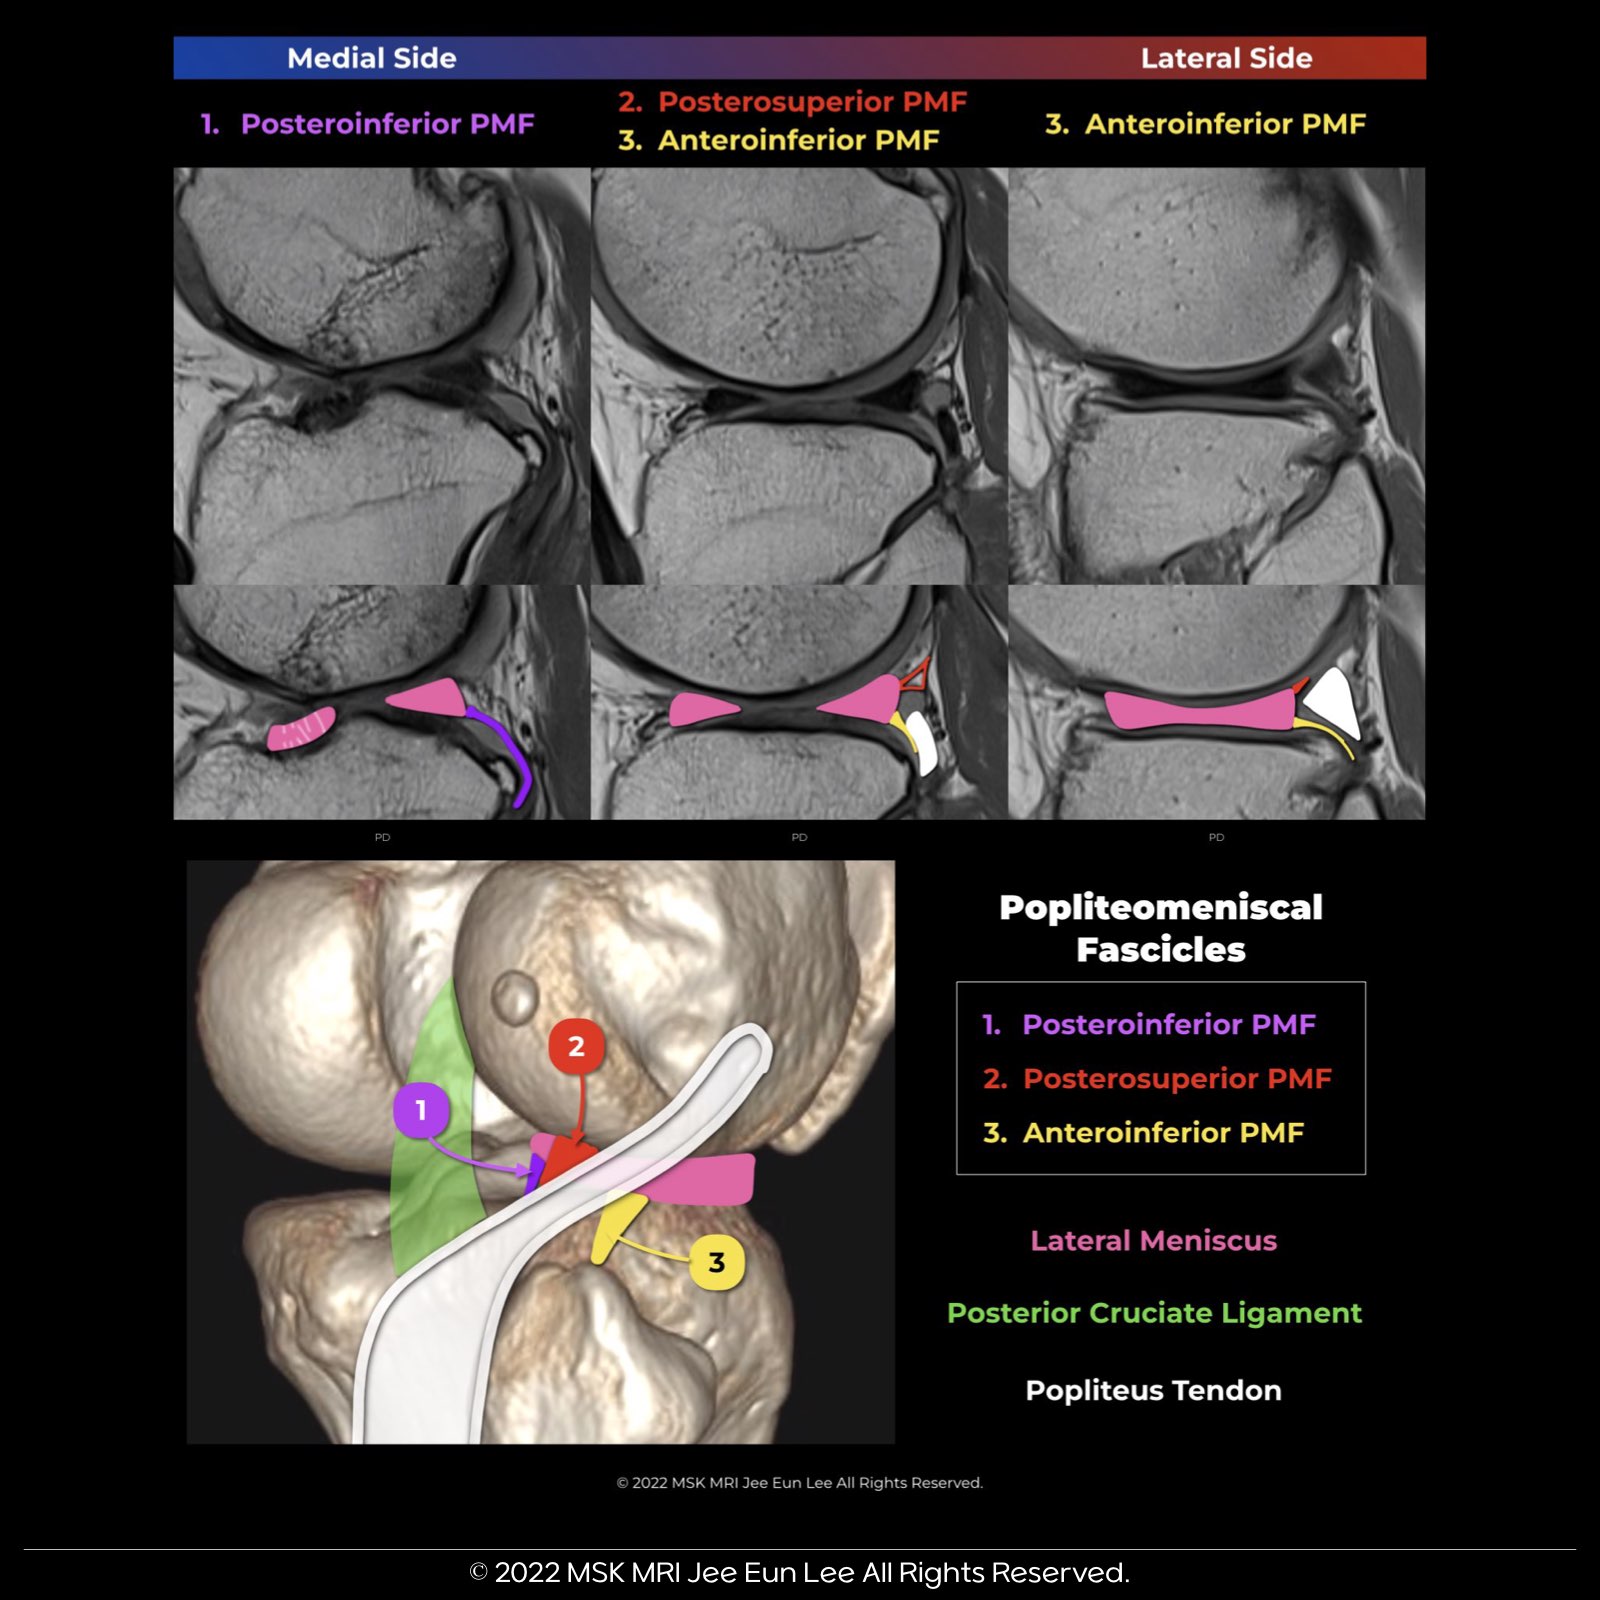

| Fascicle | Location and Appearance |

| Anteroinferior Popliteomeniscal Fascicle |

Visible on sagittal slices near the fibular head; extends posteroinferiorly from the lateral side of the lateral meniscus (LM) and merges with the popliteus tendon; conjoined attachment with the popliteofibular ligament at the fibula’s styloid process; variable appearance. |

| Posterosuperior Popliteomeniscal Fascicle |

Extends from the superior margin of the LM's peripheral posterior horn to the posterior joint capsule, above the popliteus tendon; visualized medial to the anteroinferior fascicle, especially as the popliteus tendon penetrates the meniscocapsular junction. |

| Posteroinferior Popliteomeniscal Fascicle |

Least consistently visualized; near the posterior horn's root; extends from the inferior margin of the LM posteroinferiorly to a capsular extension of the popliteus tendon; in cross-section, resembles a torn inferior flap of the meniscus. |